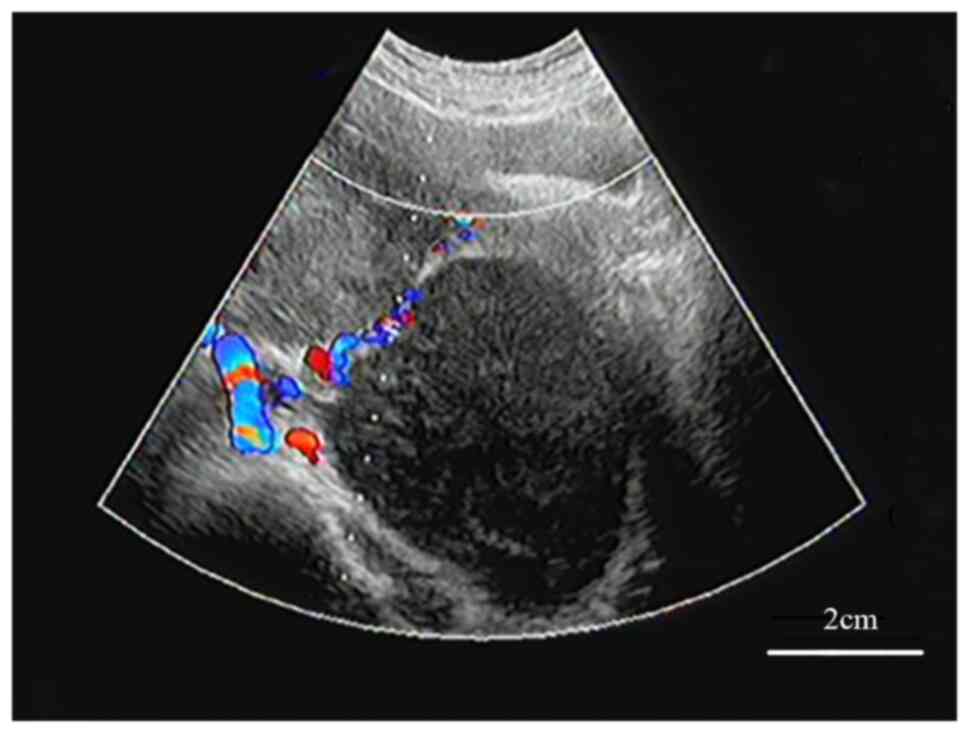

Double‑hit primary lymphoma (MYC and BCL2) in the bilateral ovary: A case report

Lymphoid neoplasm with 18q21.3/BCL2 and 8q24/MYC translocation to immunoglobulin genes as dual‑hit lymphoma in female bilateral ovaries is rare and has a poor clinical outcome. The present study reported on the case of a 33‑year‑old female, who was admitted to the hospital due to lower abdominal distension aggravated during defecation but with no obvious inducement. The B‑ultrasound revealed bilateral adnexal solid masses and the pathological examination indicated advanced B‑cell lymphoma (HGBL) with MYC and BCL2 gene rearrangement. The patient then received R‑CHOP treatment, but the effects were poor. Rare extranodal HGBL presentations with MYC and BCL2 rearrangement should be considered in the differential diagnosis of masses at unusual sites, such as the adnexa. Due to their aggressive nature, early and prompt recognition of these lymphomas is essential for appropriately administering therapies.